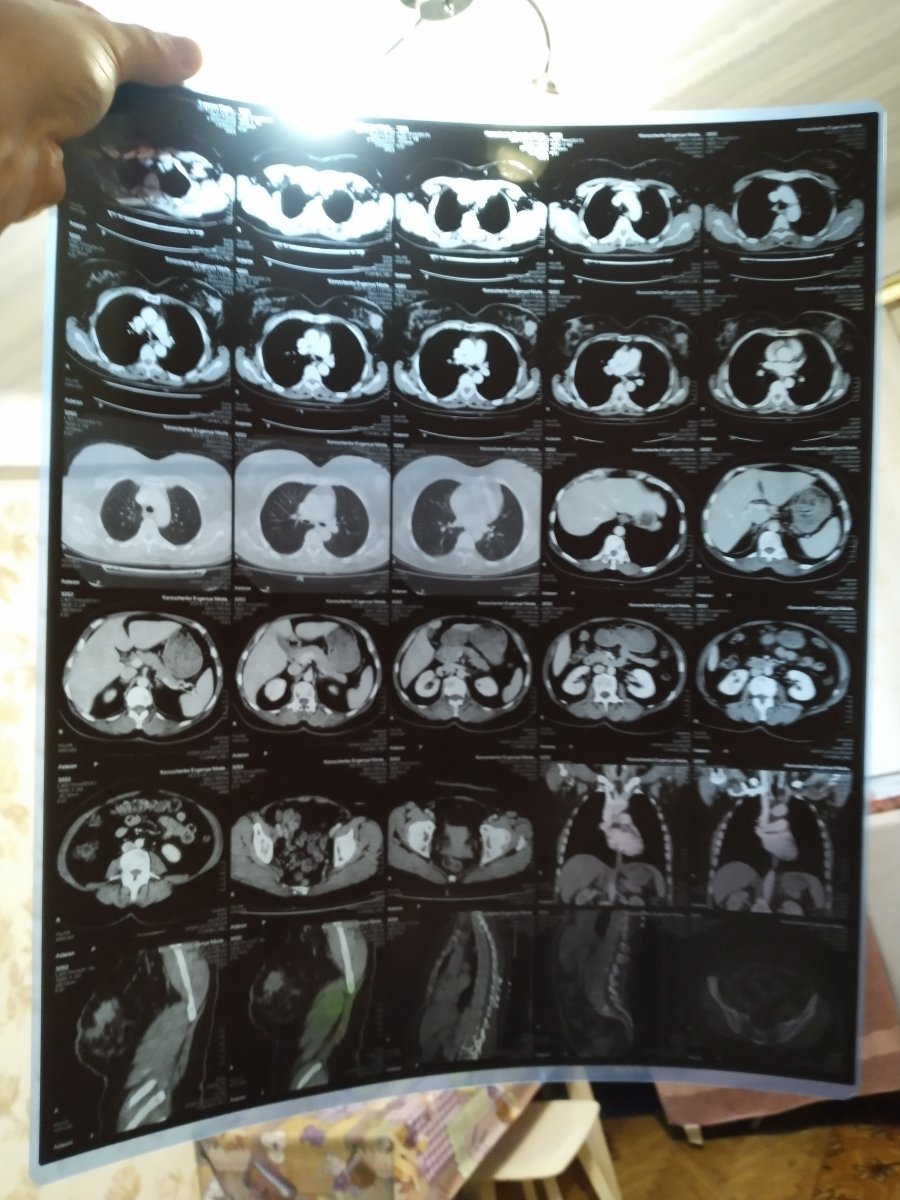

Маму я забрал в Киев, будем лечить в национальном институте рака нашол хорошего врача, вас я прошу о материальной помощи, если есть такая возможность извините заранее что беспокою , но ради жизни и здоровья мамы я готов на всё, стучюсь везде, где только можно. Белое неровное пятно на снимке это и есть та зараза которая угрожает её жизни , стадия ещё пока 2 но данное новообразование очень агрессивно и важно начать лечение уже сейчас. Одним нам не справиться пожалуйста помогите, может кому что надо из моих лотов продам с хорошей скидкой.

За любую помощь буду благодарен до конца жизни моя карта приват 4149609003427152 Корощенко Евгений Иванович